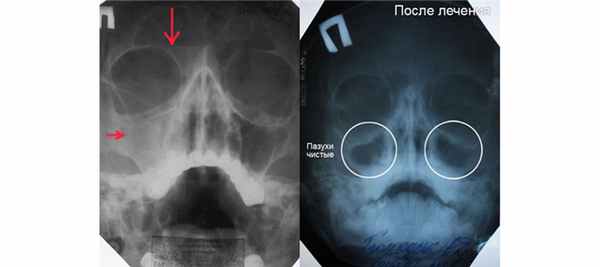

Ниже вы видите снимок гайморита до и после лечения. Рентгенограмма расшифровывается лечащим врачом, либо рентгенологом.